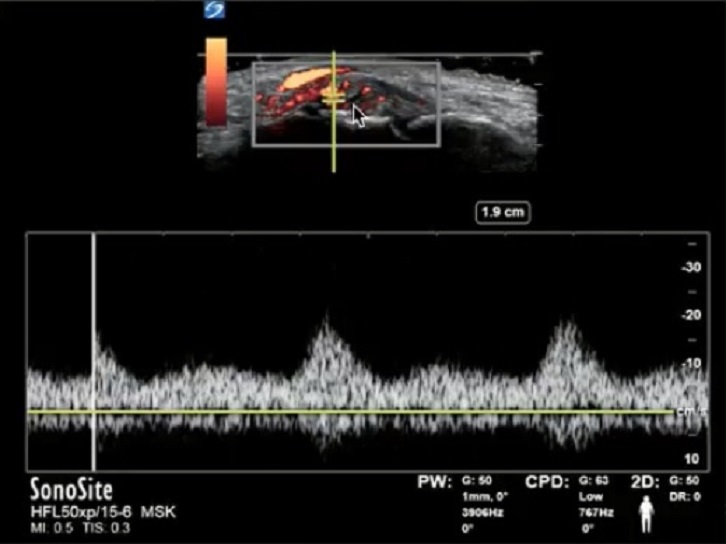

Gout 2 Color Image